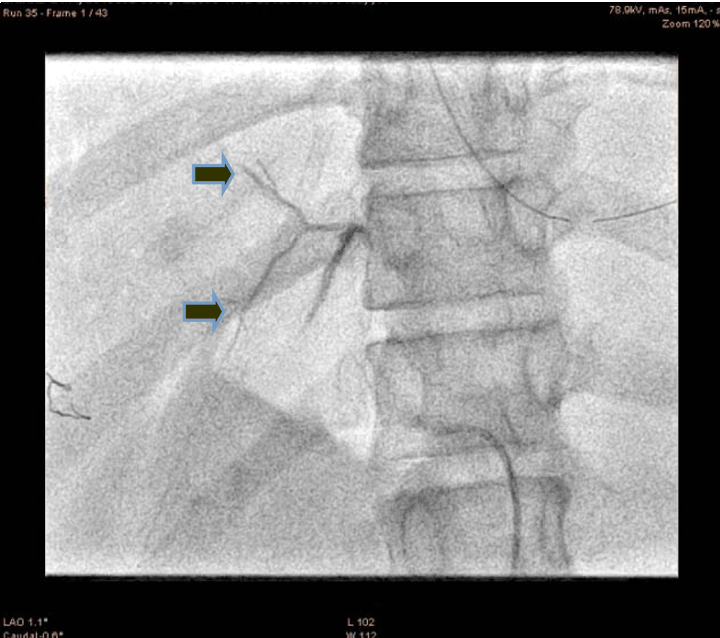

A 21-year-old male presented to the emergency department with alleged history of fall from height of about 10 feet three hours back. The patient was fully conscious and oriented with patent airway and normal breathing and ventilation. On examination, hypotensive (blood pressure 70/50 mmHg), tachycardia (110 bpm) and generalized abdominal tenderness were found. Focused assessment with sonography for trauma (FAST) was positive. So an emergency ultrasonography and contrast-enhanced computed tomography (CECT) scan of the abdomen were done which confirmed significant hemorrhage consistent with a grade III injury by the American Association for the Surgery of Trauma Organ Injury Scale. The patient was resuscitated and shifted to the operation theatre for an exploratory laparotomy, laceration of 4x2 cm with active hemorrhage were noted, the surgeon was not able control the hemorrhage successfully. So the patient was shifted to cath lab. An angiogram of superior mesenteric artery (SMA) showed bleeding from accessory hepatic artery (Figure 1). The diagnostic catheterization of accessory hepatic artery, followed by gel foam infusion to the accessory hepatic artery (Figure 2) and (Figure 3). Figure 4 shows the distal part of accessory hepatic artery occluded. Figure 5 shows occluded right artery following embolization. Repeat arteriography confirmed the occlusion of the vessel. The patient was then transferred to the ICU and transfused one unit of whole blood. He remained hemodynamically stable thereafter, without significant decrease in hematocrit. The patient gradually improved over the next several days and was discharged after two weeks. Follow-up CT scan one month after discharge showed a mild hematoma with no evidence of any infection or complication of the embolization procedure.

Figure 2: Diagnostic catheterization of accessory hepatic artery (arrow showing the artery).